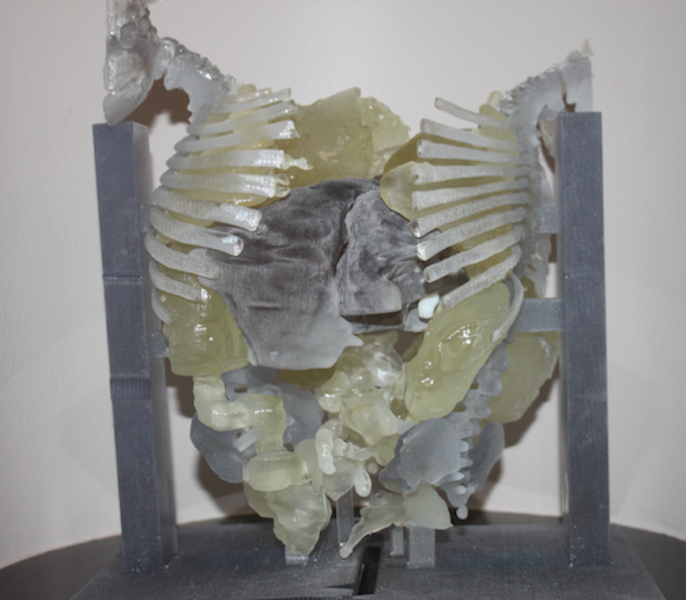

To make a good framework for filling in missing bone, mix at least 30 percent pulverized natural bone with some special man-made plastic and create the needed shape with a 3-D printer. That’s the recipe for success reported by researchers at The Johns Hopkins University in a paper published online in ACS Biomaterials Science & Engineering.

Science fiction offers a lot of ideas for creating new body parts on demand, and the advancement of 3-D printing (also ...